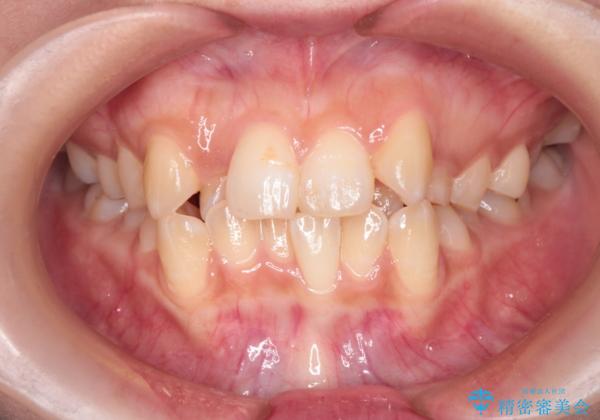

- 患者様は、歯並びのガタガタ(重度の叢生)を改善したいとのことで来院されました。診察すると、歯列のスペース不足が著しく、前歯が重なり合い、噛み合わせにも影響が出ている状態でした。歯をきれいに並べるためには抜歯によるスペース確保が不可欠と判断し、上下の小臼歯4本を抜歯したうえで、目立ちにくい審美ワイヤー矯正(白いワイヤーと透明ブラケット)を用いた治療計画を立てました。

抜歯によって歯を動かすためのスペースを確保。その後、審美ワイヤー矯正を用いて歯を1本ずつ適切な位置に誘導しながら、噛み合わせのバランスも整えていきました。時間はかかりましたが、ガタガタの歯並びがきれいに整い、機能的にも審美的にも満足のいく仕上がりとなりました。患者様からは「歯並びが劇的に改善し、見た目だけでなく噛みやすさも向上した」と喜びの声をいただきました。